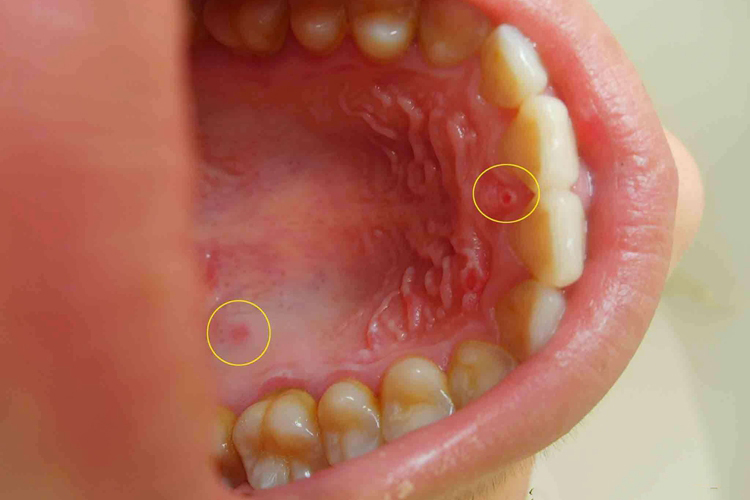

成人患手足口病可表现为发热,体温38℃-39℃,伴咽痛及口腔疼痛,食欲不佳。手、足、口腔、臀部可出现疱疹。口腔黏膜初为小疱疹,溃破后形成溃疡,多位于舌、颊黏膜及硬腭处。